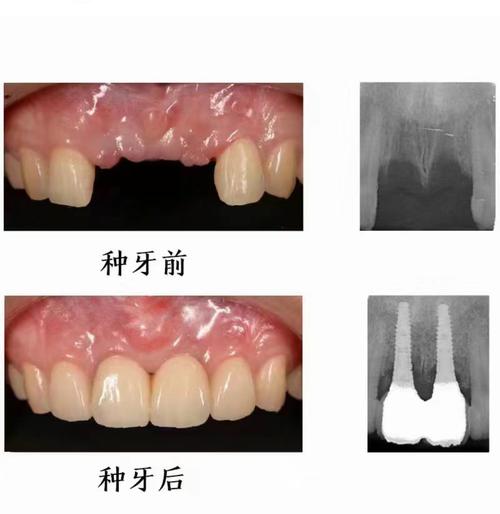

- 舒适度高,美观自然:修复后的牙冠与邻牙颜色、形态匹配,无需摘戴,无异物感,同时改善因缺牙导致的凹陷或衰老面容。